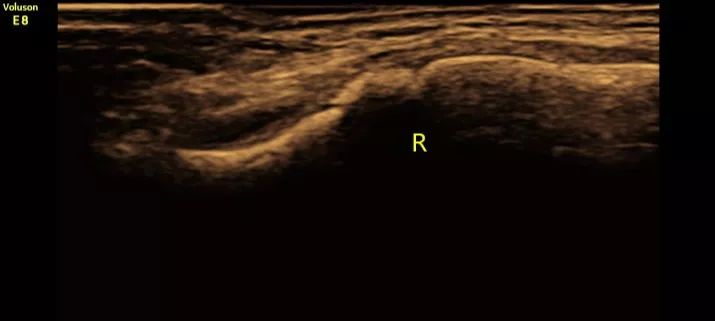

(图1:超声二维清晰显示右侧锁骨骨折断端,骨皮质连续性中断、断端错位。)

①直接征象:超声二维显示锁骨骨皮质连续性中断,新鲜错位骨折时断端显示清晰,愈合期骨折处显示增厚、模糊;